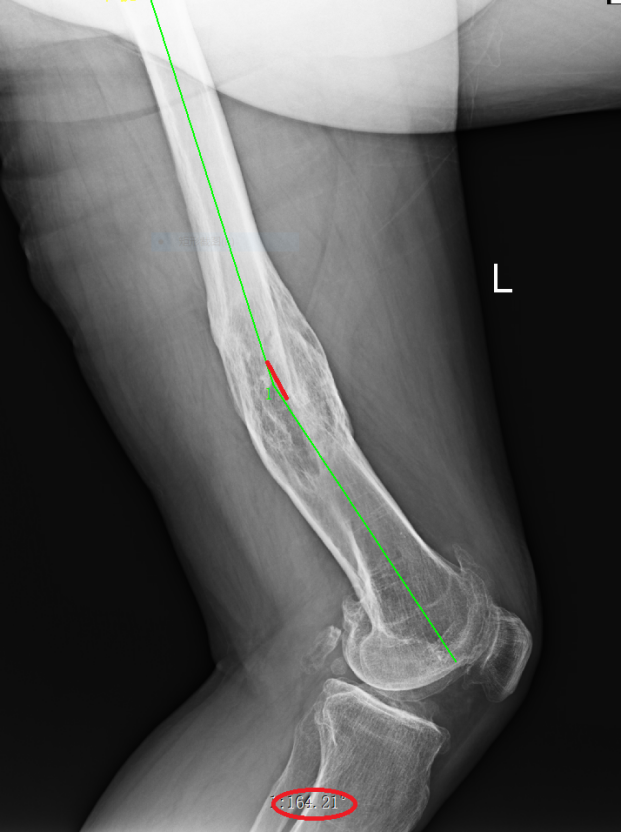

武明鑫教授為其仔細(xì)體格檢查,發(fā)現(xiàn)患者左大腿中下段外側(cè)可見一處12cm陳舊性切口疤痕,膝關(guān)節(jié)內(nèi)翻畸形,大腿中下段向外成角,膝關(guān)節(jié)內(nèi)外側(cè)局部壓痛,內(nèi)側(cè)尤為明顯,未觸及骨擦感及反?;顒?,肌力Ⅳ級,肌張力降低,左下肢較右下肢縮短約5.0厘米。拍X射線片檢查示:1.左股骨中下段骨質(zhì)膨隆并股骨彎曲,考慮是左股骨中下段骨折畸形愈合。2.左側(cè)膝關(guān)節(jié)退行性變。

術(shù)前X線片(向后成角17°)

術(shù)后復(fù)查X線片影像(側(cè)位)